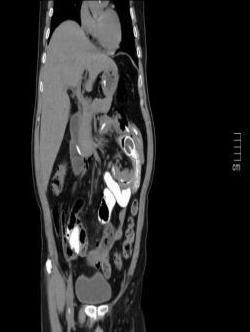

• 单侧双通道内镜下椎间盘切除术治疗钙化型腰椎间盘突出症的临床疗效分析

摘要:目的 观察单侧双通道内镜(UBE)下椎间盘切除术治疗钙化型腰椎间盘突出症(CLDH)的临床疗效。方法 回顾性分析2020年1月-2022年1月在该院行UBE下腰椎间盘切除术的25例单节段CLDH患者的临床资料。记录手术时间、术后住院时间和术后并发症情况。采用腰腿痛视觉模拟评分法(VAS)评分、腰椎日本骨科协会(JOA)评分和Oswestry功能障碍指数(ODI),评估术前、术后3 d、术后1个月和末次随访的临床疗效。末次随访时,采用改良Macnab标准,评估优良率。结果 术后随访12~24个月,平均(15.60±2.60)个月。手术时间为(58.67±10.73)min,术后住院时间为(4.65±0.63)d。术后3 d、术后1个月和末次随访时的VAS评分和ODI明显低于术前,JOA评分明显高于术前,差异均有统计学意义(P < 0.05)。末次随访时,根据改良的Macnab标准,15例为优,9例为良,1例为可,优良率为96.00%(24/25)。术后并发症:1例神经根腹侧硬膜囊撕裂,长度约5 mm,未行硬膜囊修补术,术后嘱患者卧床5 d,给予补液治疗,患者下床活动未诉头痛等不适,术后MRI显示:未见硬膜外大量积液;1例出现下肢感觉障碍,给予营养神经药物对症治疗,术后1个月随访时恢复。术后影像学检查显示:游离钙化组织基本被完全切除,神经根得到充分减压。末次随访时,未发现复发病例。结论 UBE下腰椎间盘切除术治疗CLDH安全、有效,值得应用于临床。